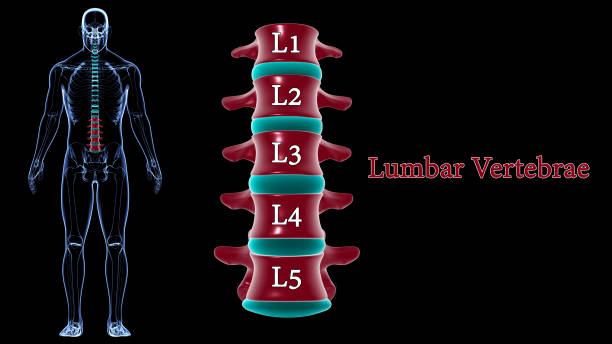

La lumbalgia aguda es un dolor de gran intensidad ubicado en la zona baja de la espalda que llega a aparecer de manera súbita, por lo general, tras un esfuerzo físico, una mala postura o un movimiento brusco, pero no todo dolor de espalda es exactamente igual.

- Dolor “en cinturón”: que se corre hacia las nalgas o piernas.

En nuestra Clínica InDolore, nuestro enfoque como especialistas en tratamiento del dolor en Puebla es llevar a cabo un diagnóstico diferencial de gran precisión. Esto quiere decir que llegamos a reconocer si el dolor es puramente muscular o si existe una compresión nerviosa, como en el caso de una estenosis o una hernia discal que necesita una intervención más avanzada.